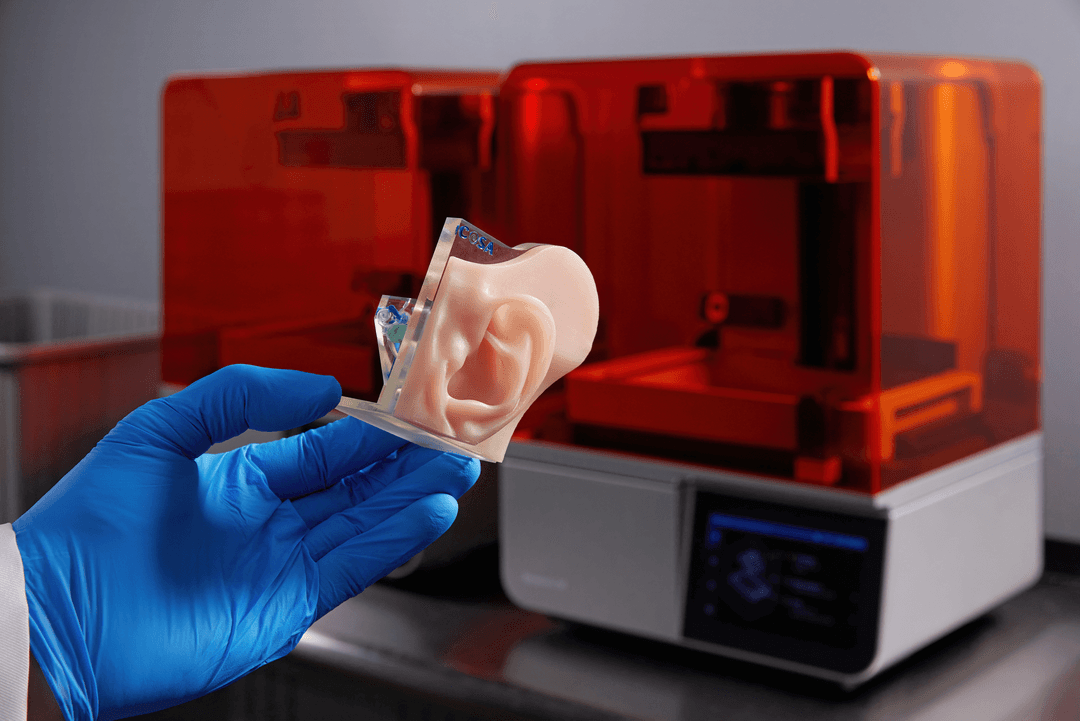

To reproduce the complex three-dimensional structures found in organic in-vitro environments, cells need support structures, called scaffolds. In the laboratory setting, these scaffolds are made from a porous, biocompatible polymer. SLA 3D printing can be used to create molds for the scaffold polymer.

To create a scaffold mold for a 3D cell culture, first the researcher will determine the intended shape, and 3D print a corresponding negative model. This negative is then used to cast a silicone mold which can be used to form the scaffold polymer. A similar process of 3D printed master, silicone mold, and end-use polymer product is shown below in this fabricated model of a multi-channel blood vessel.